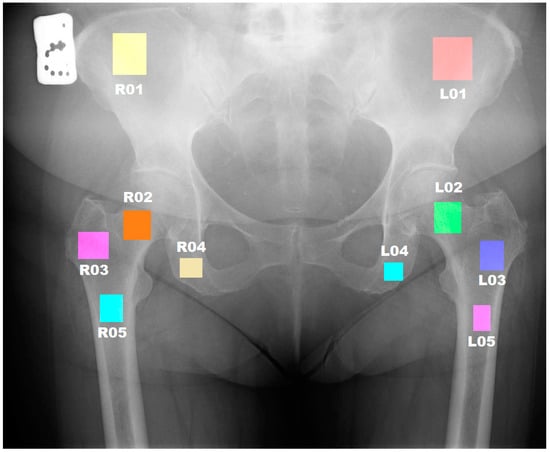

To annotate the ROIs (Regions of Interest) on the preselected images, the qMaZda software (release version 19.02) was used []. In each radiograph, rectangular ROIs were selected to correspond to specific anatomical structures. Where endoprostheses were present, the ROIs were refrained from being marked, resulting in a lower number of analyzed areas. A detailed description of the ROI delineation process is provided in Figure 1 and Table 1.

Figure 1.

Regions of interest are depicted on the radiograph.